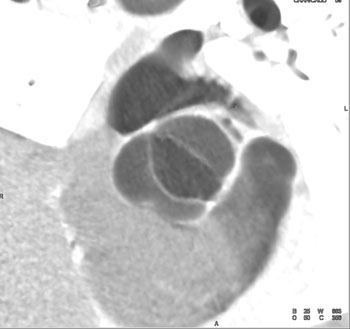

|  | Question 1: 46 year old male with atypical chest pain. What’s the best diagnosis based on the image set? |